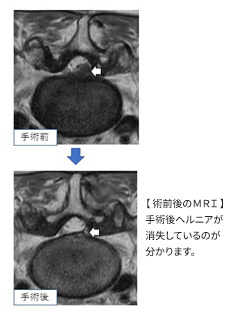

しかし下肢痛がとても強い場合、足に力が入らなくなった場合、3か月以上保存加療しても改善しない場合などは手術適応があります。当科では脊椎内視鏡システムを導入することで、より安全なヘルニア摘出術を行っています。

手術出血はほとんどなく、傷は医療用テープで固定するため抜糸の必要もありません。

術後は翌日より歩行訓練でき、入院期間は1週間以内です。早期退院も可能ですが、リハビリなどを希望される場合は自信がつくまでトレーニングすることも可能です。

脊椎内視鏡は、皮膚切開の小ささ(約2㎝)、背筋群など軟部組織に対するダメージが少ないことに加え、 神経組織が拡大された明るい視野で手術が可能です。 また、斜視鏡を用いることで、より広い範囲が見えることが大きな特徴です。スポーツ選手や若い方で傷を小さく、回復を早くしたい方にはとても有効な手術方法です。